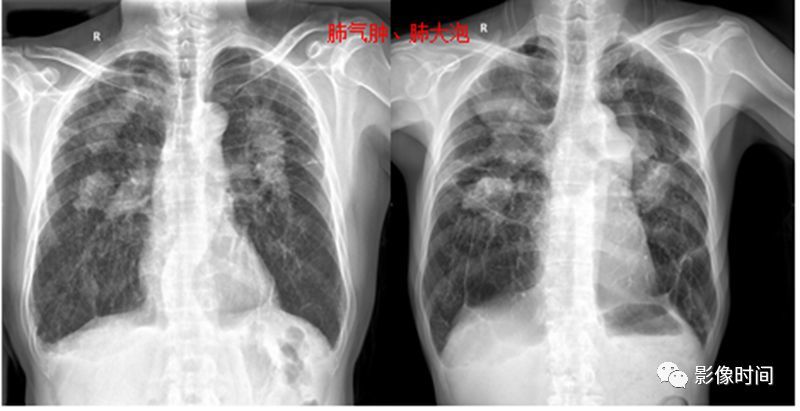

肺气肿的影像诊断

肺气肿胸片影像

肺气肿的胸片表现